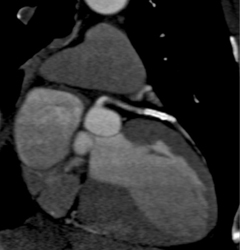

Stent in LAD and Diseased RCA